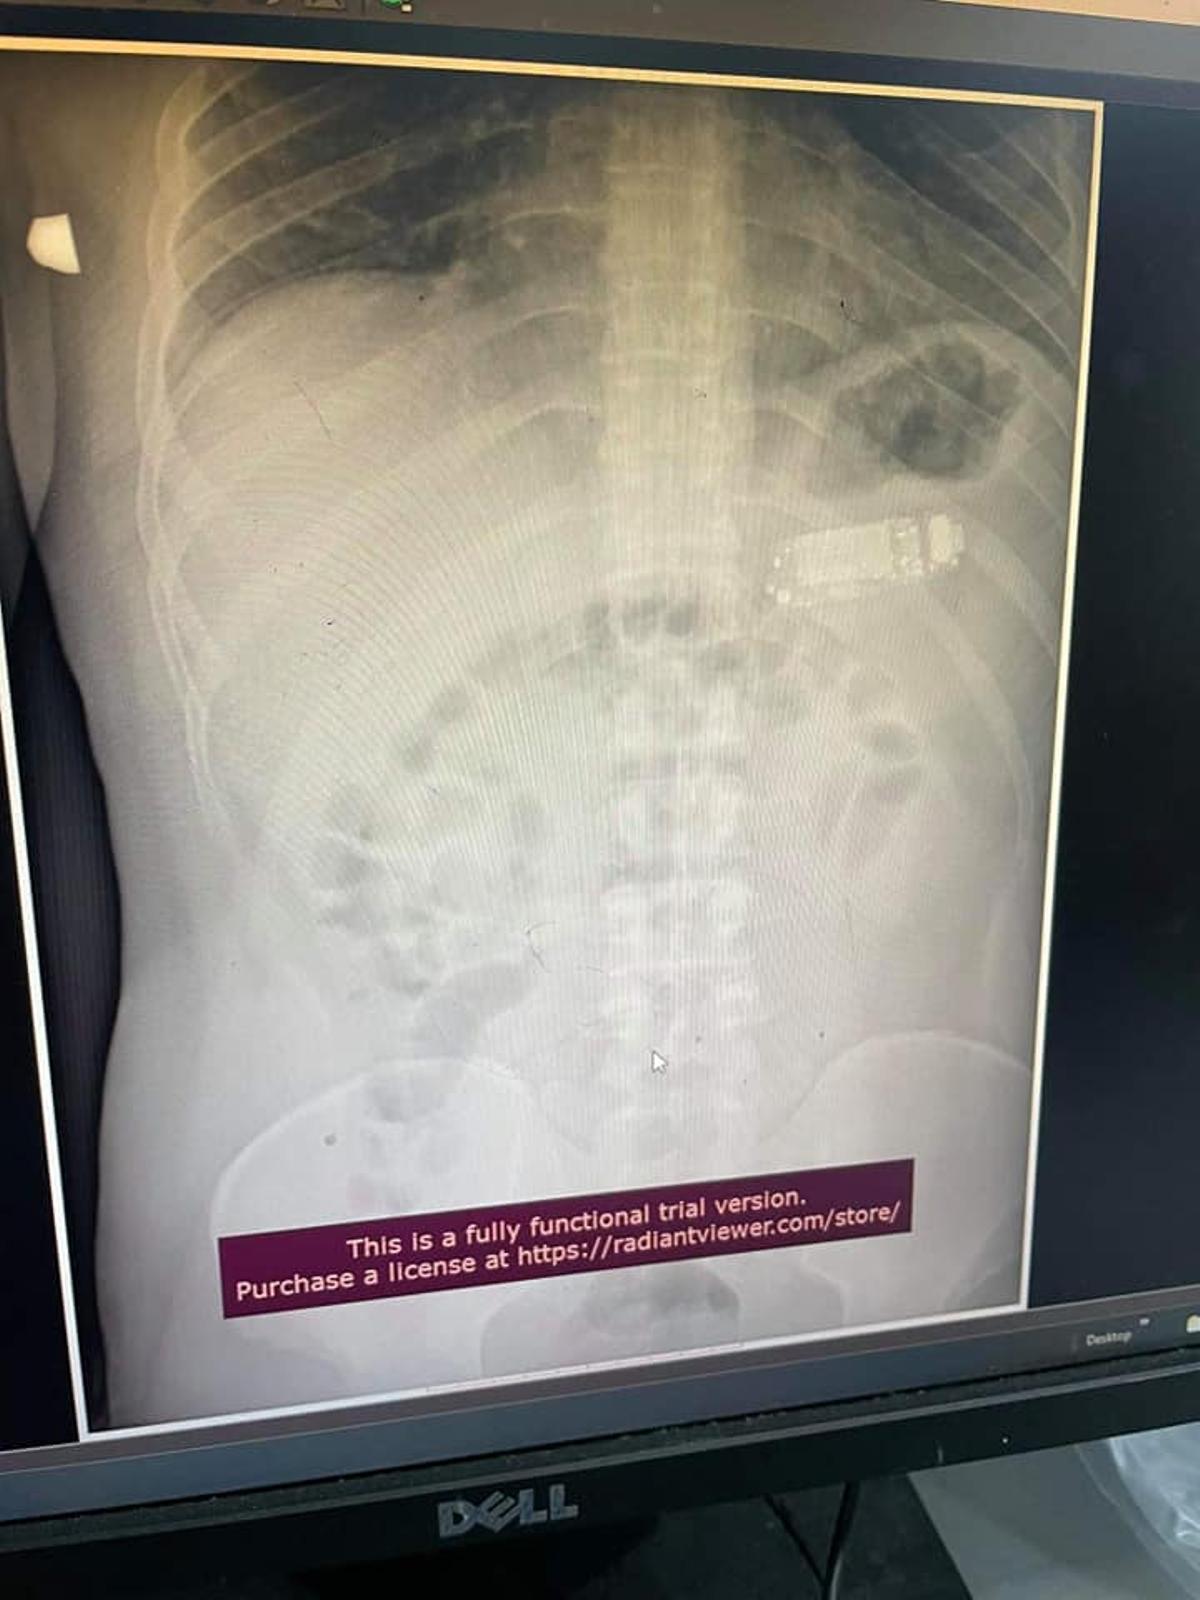

La radiografía donde se aprecia el teléfono dentro del estómago del paciente

Ver para creer. Los médicos de un hospital de Pristina, la capital de Kosovo, debieron alucinar al descubrir el motivo por el que un paciente acudió refiriendo dolor estomacal. El hombre, de 33 años, se había tragado, por razones que no han trascendido, nada menos que un teléfono móvil Nokia 3310.

Lógicamente tuvo que ser intervenido de urgencia, ya que los facultativos temían que los ácidos gástricos empezaran a descomponer la batería del dispositivo, algo que sería crítico para la supervivencia del paciente.